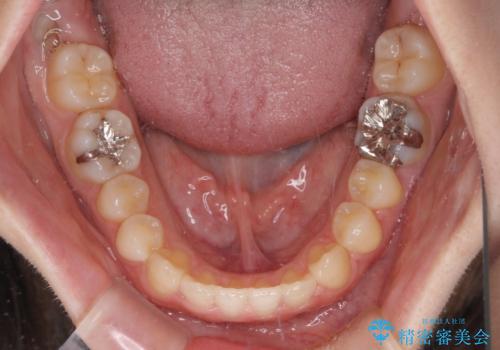

前歯のクロスバイト インビザラインによる矯正治療

- 前歯のクロスバイトとデコボコを気にして来院された患者様です。

骨格的に下顎前突傾向であるため、自己管理が煩わしくないようであれば、インビザラインによる矯正治療がお勧めとなります。

インビザラインを用い、下顎歯列を後方に移動させながら全市の被蓋を改善し、歯並びを整えていくこととしました。

途中マウスピースが使用できず、来院されない期間があり、治療期間は長くかかりましたが、無事に治療を終えることができました。